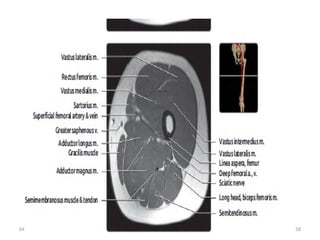

MRI

 T1 or PD help distinguish fluid in vessels from

nerves.

 Correlate with fluid-sensitive sequences.

 Fat fascicles are especially prominent in

sciatic nerve.

• The abundant fat around the fascicles and the nerve itself

makes these structures clearly visible on T1-weighted images.

• Normal fascicular shape was defined as clustered similar-sized

rounded structures on T1 MR images.

• The normal nerve shows a fascicular appearance.

• It has signal intensity from isointense to minimally

hyperintense with respect of the adjacent muscle.

• The perineural fat tissue has a homogeneous signal and a

separation plane with the adjacent structures.